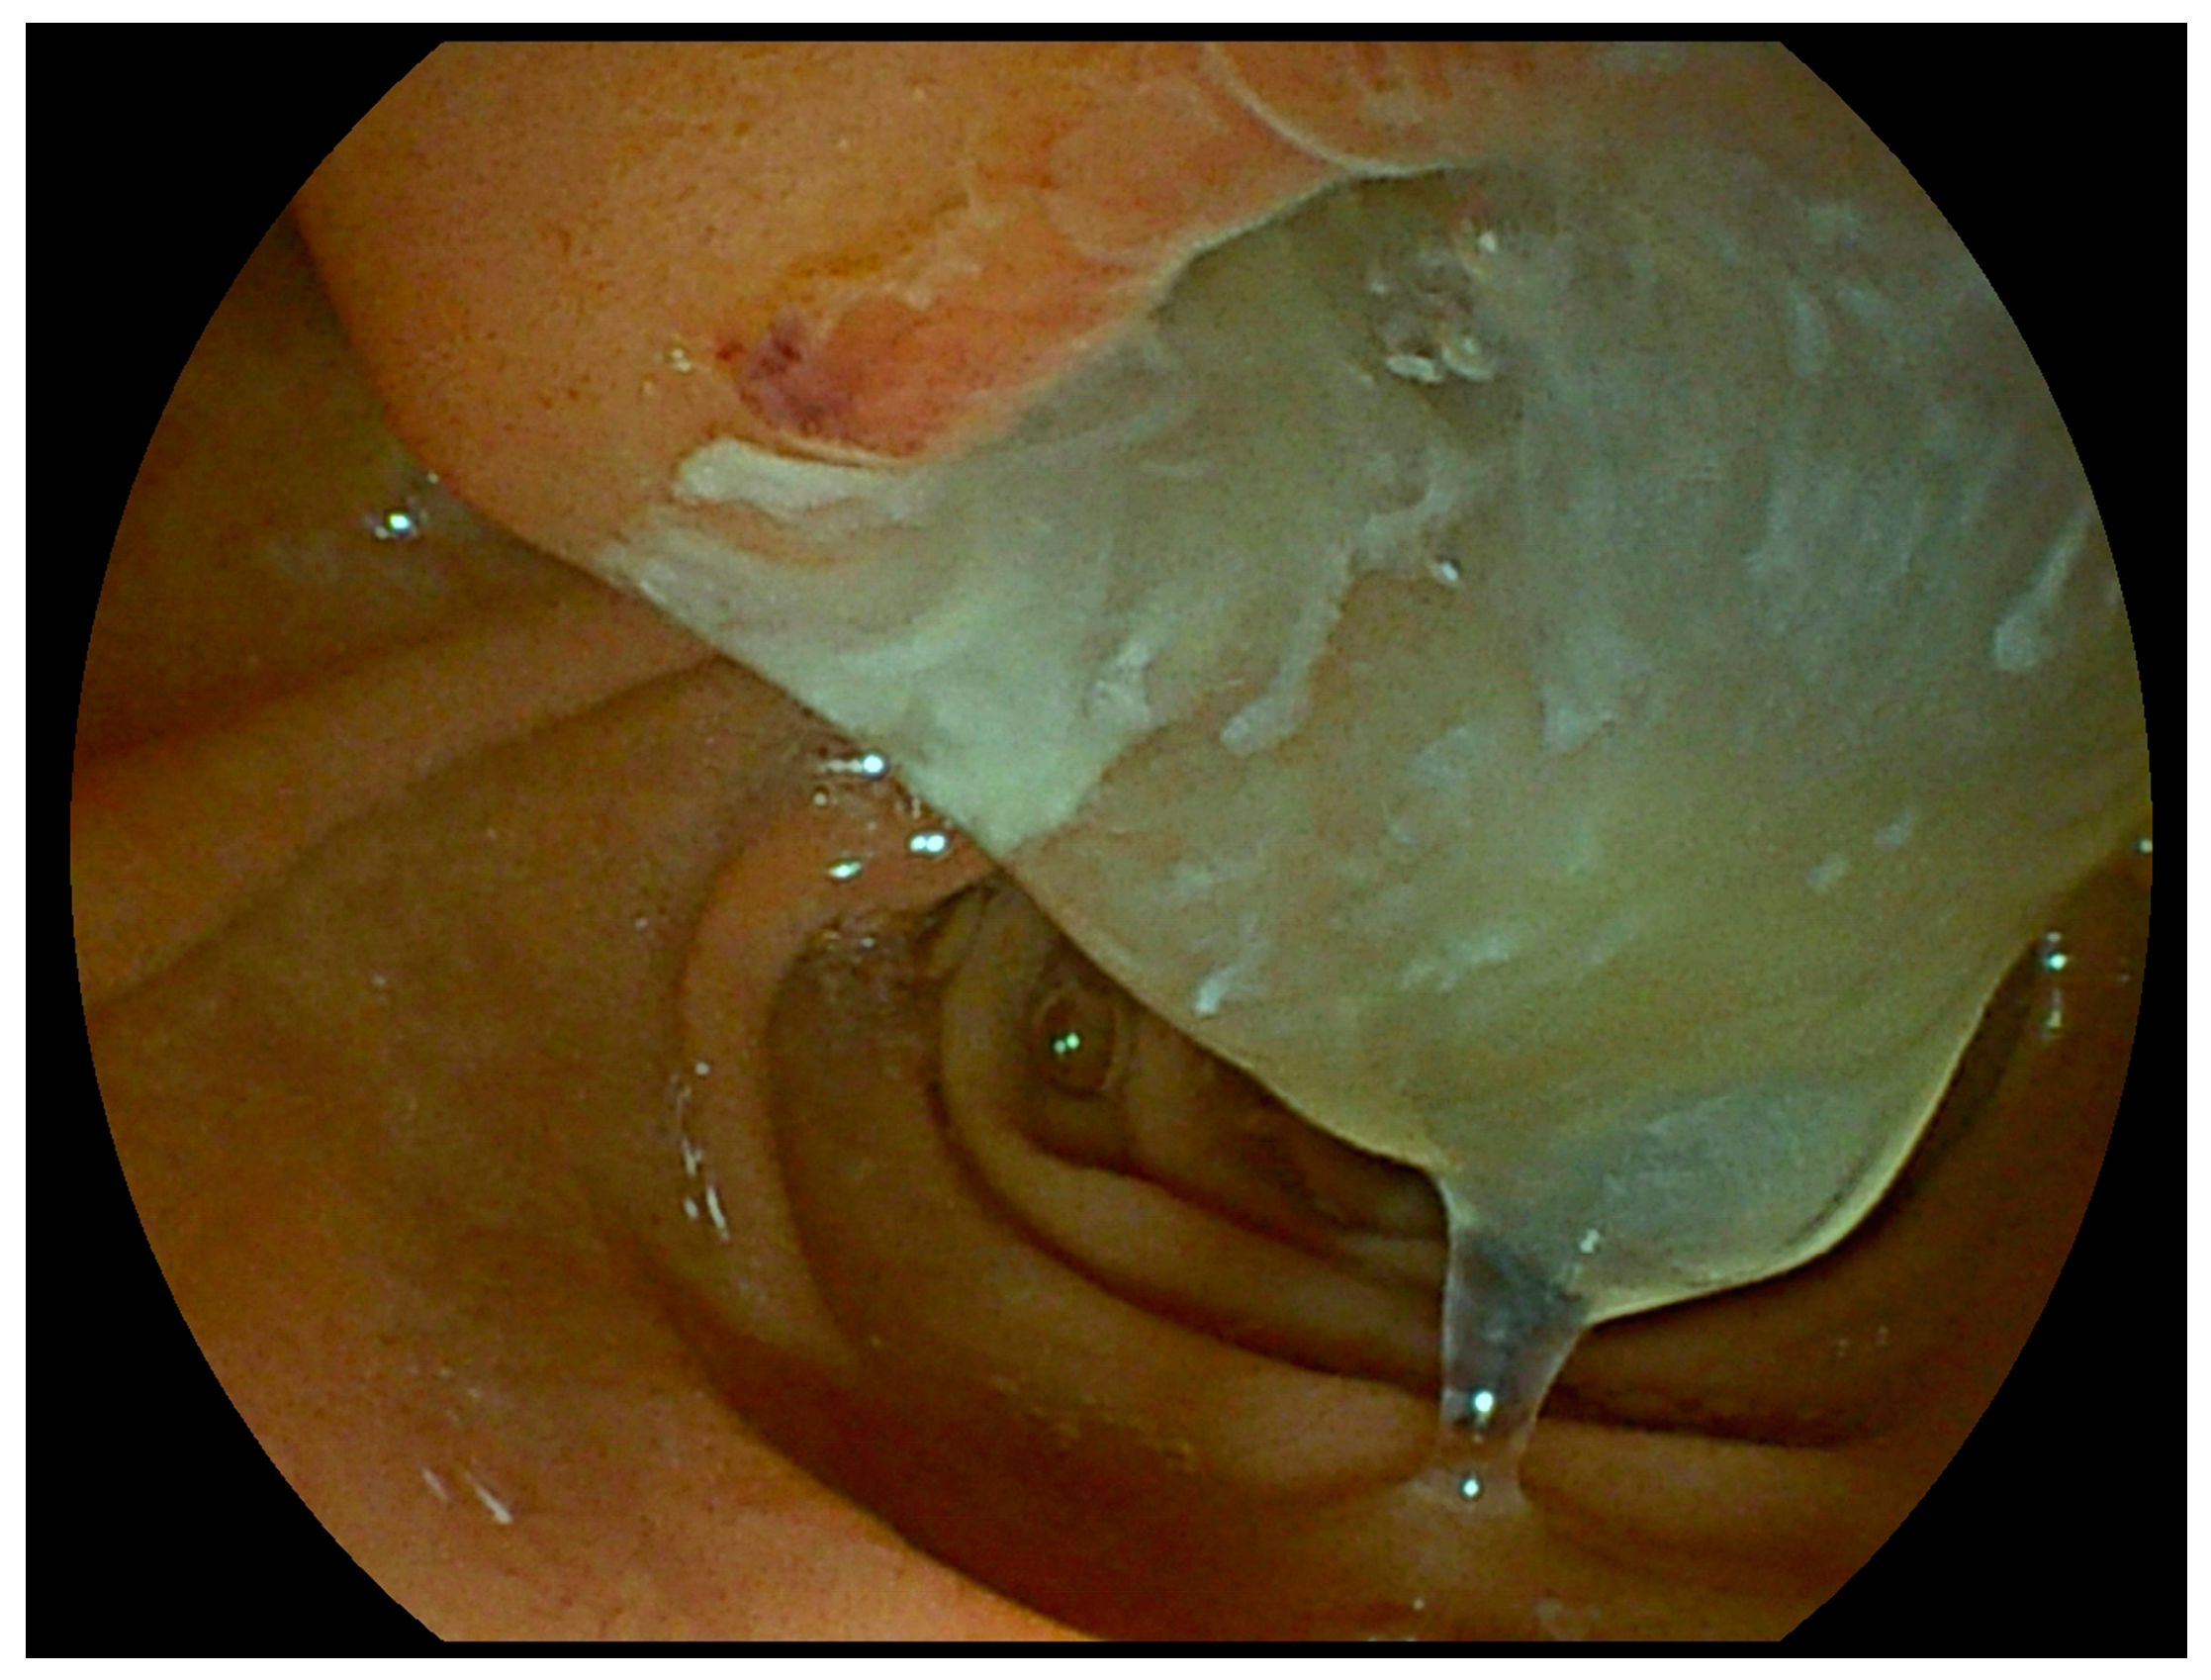

| Fish mouth papilla | IPMN | Endoscopy | - <30% of cases - More common in main-duct and mixed IPMN - Best assessed by duodenoscope |